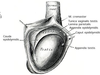

What is shown here?

Bell Clapper Deformity

- Risk factor predisposing someone to torsion (intravaginal)

What is intravaginal torsion?

Torsion distal to tunica vaginalis attachment

- Bell-Clapper or horizontal lie predisposes to torsion